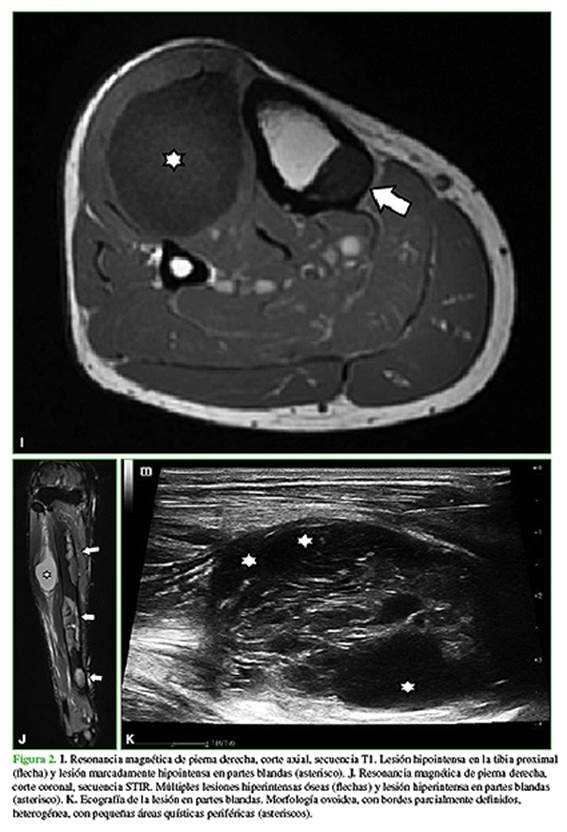

En febrero de 2020, consulta a un traumatólogo de nuestro centro. En el examen físico, la movilidad de la cadera y la rodilla es completa, sin dolor en el miembro inferior derecho. Además, se palpa una tumoración en la zona anteroexterna proximal de la pierna derecha de aproximadamente 8 cm, profunda, elástica, no dolorosa (Figura 1) que, según el paciente, tenía desde los 17 años de edad y su crecimiento era lento. Se solicitan nuevas radiografías y una resonancia magnética de cadera y pierna, y una ecografía de la masa de partes blandas en la pierna (Figura 2).

Las radiografías son normales, aunque los mixomas intramusculares se pueden manifestar con calcificaciones no específicas en partes blandas. En la ecografía, los mixomas intramusculares se visualizan como masas ovoideas, poco definidas e hipoecoicas, con posibles áreas quísticas. En la tomografía computarizada, aparecen como lesiones hipointensas con pared que las separa del tejido muscular. En la resonancia magnética, se visualizan como lesiones hiperintensas en las secuencias T2, gradiente de eco o STIR. Las secuencias T1 muestran baja señal.2,6-9